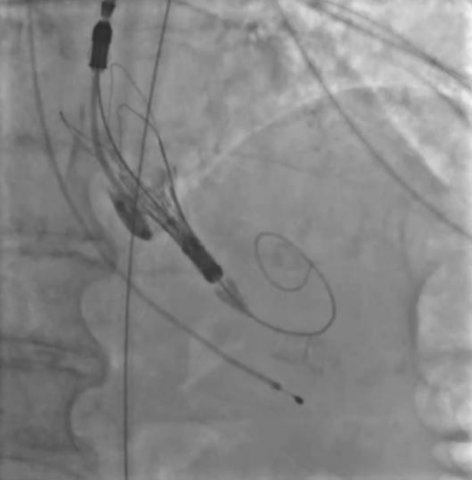

Рис. 2. Пациентка А. В момент проведения протеза визуализируется массивная аортальная регургитация.

В представленных клинических случаях по данным ЭхоКГ у всех пациенток наблюдался феномен малого объема ЛЖ (табл. 1), однако подход к проведению оперативного вмешательства различался. Так, у первой пациентки причиной неудачной ТИАК послужила сложившаяся совокупность факторов. Развившийся гемодинамический коллапс можно объяснить тем, что, вероятно, произошла объемная перегрузка ЛЖ за счет возросшей аортальной регургитации (подтверждается при выполнении аортографии (рис. 1), что в сочетании с малой полостью и диастолической дисфункцией привело к молниеносному развитию острой левожелудочковой недостаточности. В Клинических рекомендациях по ХСН (2024) подчеркивают, что у пациентов с диастолической дисфункцией и малым объемом ЛЖ риск гемодинамического коллапса значительно возрастает, особенно при наличии сопутствующей легочной гипертензии [8]. В тот момент единственным возможным решением сложившейся ситуации стало быстрое заведение и установка биопротеза. Однако даже после имплантации клапана восстановления гемодинамики не произошло. При развитии подобного сценария выполняется продвинутая сердечно-легочная реанимация (СЛР), при этом краеугольным камнем успешной СЛР у пациентов после имплантации протеза является выполнение качественных компрессий, позволяющих создать достаточное пульсовое давление, необходимое для обеспечения запирательной функции протеза и разгрузки ЛЖ. К сожалению, наличие кифосколиотического изменения грудного отдела позвоночника не позволили выполнять эффективные компрессии ни мануально, ни с помощью механического устройства для непрямого массажа сердца, вследствие чего наступившая острая левожелудочковая недостаточность не была скомпенсирована работой протеза клапана, что и привело к летальному исходу. Данные аутопсии лишь подтверждают изложенную версию произошедших событий. Также нельзя исключить влияния сопутствующей желудочковой фибрилляции и выраженной легочной гипертензии на развитие неблагополучного течения ТИАК.